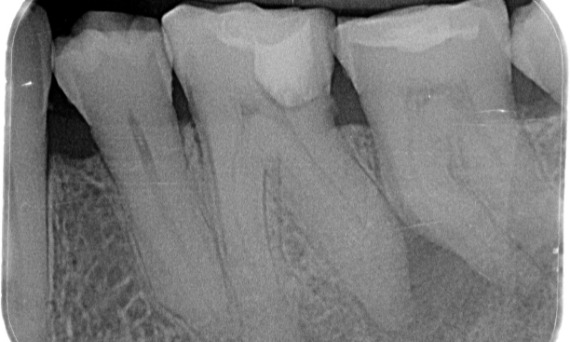

Antes: Durante la evaluación, se detectó una lesión de caries relacionada con el primer molar inferior derecho. El examen radiográfico reveló la proximidad de la lesión al cuerno pulpar, y al combinarla con la queja principal, se concluyó un diagnóstico final de pulpitis irreversible crónica.

Después: La cavidad de acceso se realizó de la forma más conservadora posible. TruNatomy fue el sistema de elección debido a la juventud del paciente. Necesitábamos conservar la mayor cantidad de dentina para aumentar la capacidad dental de superar la carga oclusal y aumentar la longevidad de la restauración final.

El Cairo, Egipto